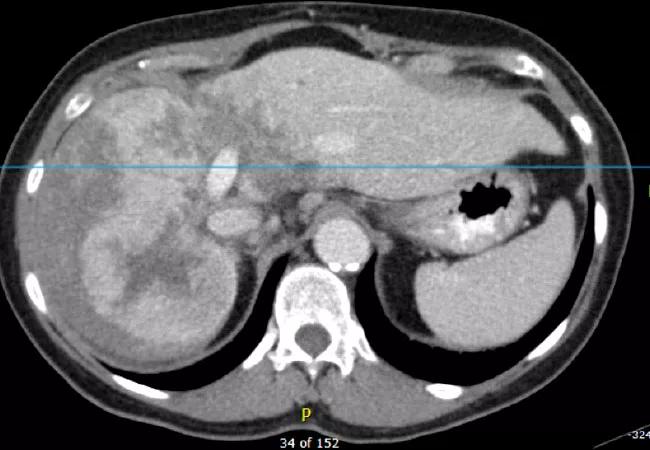

A 69-year-old woman was diagnosed with a large hepatocellular carcinoma/cholangiocarcinoma. This mixed tumor, which measured 10 cm in the right lobe of the liver, extended across the midline to a portion of the left lobe. The liver had no cirrhosis and liver function was good.